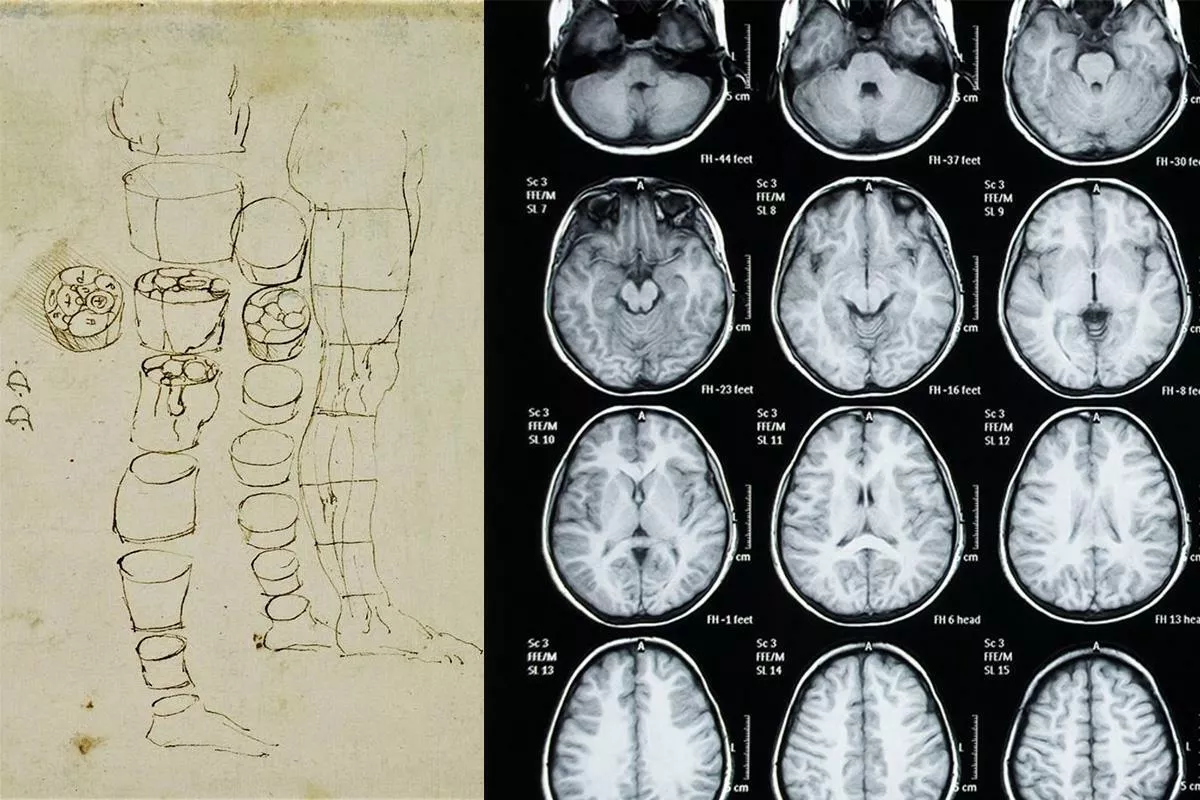

Leonardo Da Vinci, I muscoli e i tendini della parte inferiore della gamba e del piede, gessetto nero, penna e inchiostro acquarellato, 1510-11 circa. Windsor Castle, Royal Library, RCIN 919017r / Radiografia dell’arto inferiore.

Leonardo inventa anche il disegno dei corpi in trasparenza, che anticipa le moderne tecnologie di visualizzazione endoscopica. Il disegno nel foglio RCIN 919017r di Windsor rappresenta i muscoli e i tendini della parte inferiore della gamba e del piede, attraversando in progressione i vari strati epidermici, muscolari, tendinei e ossei.

Il disegno della gamba sezionata nel foglio RCIN 912627v di Windsor mostra invece le variazioni di disposizione e larghezza delle strutture interne nelle differenti altezze, in un modo simile alle odierne tomografie assiali computerizzate. “L’artista non disegna ciò che vede, ma vede ciò che disegna”, precisa Di Napoli ogni volta che sia necessario ribadire la funzione del disegno nella pratica delle arti visive. In questa sua precisazione riecheggiano le parole dello storico dell’arte Ernst H. Gombrich: “L’artista tenderà a vedere quello che dipinge più che dipingere quello che vede” (Arte e illusione, Einaudi, Torino 1965, p. 104).